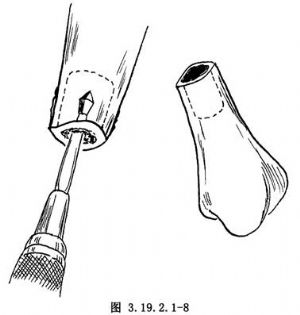

遊離骨端,切除遠、近端硬化的骨組織(圖3.19.2.1-7)。鑽通和擴大遠近端髓腔(圖3.19.2.1-8)。手法矯正脛骨向前成角畸形,並使健康的脛骨遠、近端互相嵌壓。有時需另做切口延長跟腱,以利脛骨成角畸形矯正。如腓骨完整使脛骨兩斷端分離,應另做切口,切除一段腓骨,才能使脛骨兩斷端對正(圖3.19.2.1-9)。以斯氏釘逆行法髓內固定切斷的腓骨(圖3.19.2.1-10)。這樣對脛骨的斷端也提供了良好的對位和固定作用。在手法矯正向前成角畸形時,最好使脛骨矯正到向後成角15°~20°(圖3.19.2.1-11)。